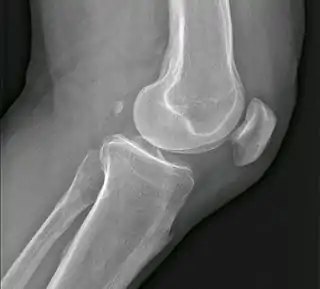

El fabela, también conocido como fabella (del diminutivo latino de faba, 'haba'), es un pequeño hueso sesamoideo que se encuentra en algunos mamíferos incrustado en el tendón de la cabeza lateral del músculo gastrocnemio (gemelos) detrás del cóndilo lateral del fémur.

![]() Fabela es la pequeña osificación en situación posterior de los cóndilo femorales. | ||

Es una variante de la anatomía normal, presente en los seres humanos entre el 10 y el 30 % de los individuos. En raras ocasiones, hay dos o tres de estos huesos (fabela bi- o tripartita). Puede ser confundido con un cuerpo suelto o de osteofitos.

El fabela es un hallazgo normal en las radiografías del perro y el gato, y ambos fabellae, medial y lateral, son típicamente presentes.